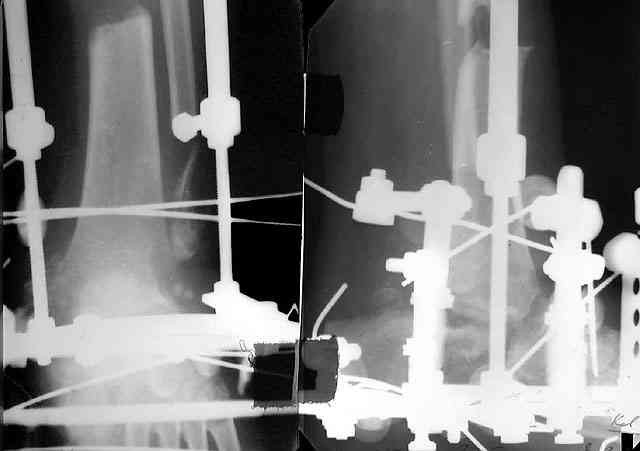

Глубокоуважаемые коллеги! Просим совета в лечении пациента с последствиями тяжелой сочетанной травмы. Пациент С., 41 года, по профессии бизнесмен, в сентябре 2005 г. пострадал в дорожно-транспортном происшествии (упал с мотоцикла). Диагноз: ЗЧМТ, ушиб головного мозга тяжелой степени. Открытый переломо-вывих левой таранной кости. Закрытые переломы лонной и седалищной костей слева. Был доставлен в НИИСП им. Н.В. Склифосовского. При ПХО раны выявлен открытый перелом левой таранной кости (III тип по Hawkins) с утратой вывихнутого тела таранной кости. Выполнена ПХО, фиксация голени и стопы стержневым аппаратом. Рана зажила без осложнений. Аппарат демонтирован через 1,5 месяца. В настоящее время больной предъявляет жалобы на боль в голеностопном суставе при нагрузке. Передвигается с опорой на костыли с дозированной нагрузкой на левую стопу.Голень и стопа фиксированы циркулярной пластиковой повязкой. Сохраняются остаточные явления ЧМТ (в виде сниженной критики к своему состоянию и определенной недисциплинированности в выполнении врачебных рекомендаций) Рентгенограммы – рис. 1, 2 (просим извинения за низкое качество рентгенограмм), схема – рис. 3. В качестве варианта хирургического лечения мы считаем возможным выполнить следующее вмешательство: артродез большеберцовой и пяточной костей в сочетании с артродезом переднего края большеберцовой кости и головки таранной кости с фиксацией спонгиозными винтами. Считаем выполнение артродеза переднего края большеберцовой кости и элементов I луча стопы необходимым для максимального восстановления опороспособности конечности. Однако выполнение операции в указанном объеме привело бы к относительному укорочению внутреннего свода стопы. Мы видим два пути решения данной проблемы: Вариант 1. Применение костного трансплантата (свободного или на сосудистой ножке) для замещения дефекта головки таранной кости и сохранения геометрии внутреннего свода стопы (рис 4). Преимущество: относительная простота операции. Недостаток: высокий риск замедленной консолидации или лизиса трансплантата. Вариант 2. Резекция участка пяточной кости с последующим остеосинтезом винтами для укорочения наружного свода стопы (рис 5, 6). Преимущества: сохранение собственного кровоснабжения всех синтезируемых участков костей. Недостатки: дополнительная травматизация, усугубление деформации стопы в виде нарушения наружного свода. Будем признательны за ваши предложения, включая возможные альтернативные варианты лечения.Заранее благодарны за добрые советы и поддержку. А. Федосов, О. Диденко, П. Иванов. Отделение множественной и сочетанной травмы НИИСП им. Н.В. Склифосовского, г. Москва.

той остеотомией, которая делается для отворачивания кожно-костного лоскута с малоберцовой костью. Фиксируем все это аппаратом (пример в приложении) около 4 мес.